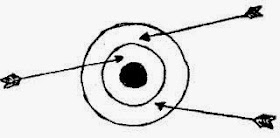

obviously dead. The head was so high up and appeared to be stuck. The abdomen

had a very abnormal contour which is quite commonly seen with those who

sustained a rupture uterus.

Considering the chance of a rupture uterus and bowel

injury, we decided to operate. On hindsight, the decision was a ill thought one.